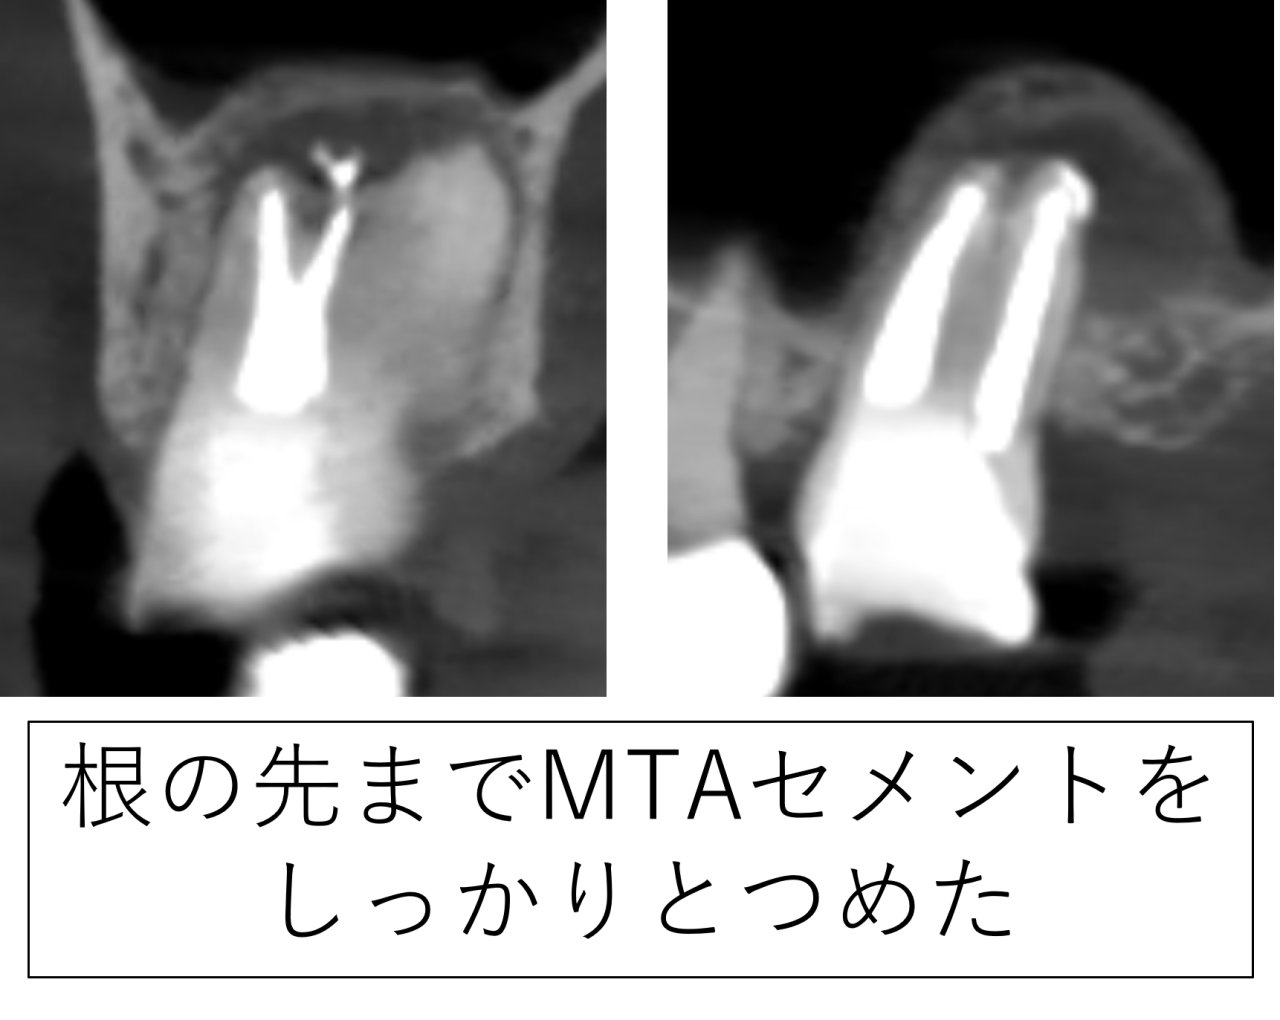

内部を十分に清掃した後、根の中を封鎖しました。本症例ではMTAセメントを使用しました。MTAは根の先を閉じる目的で用いられる材料の一つで、症例に応じて選択します。